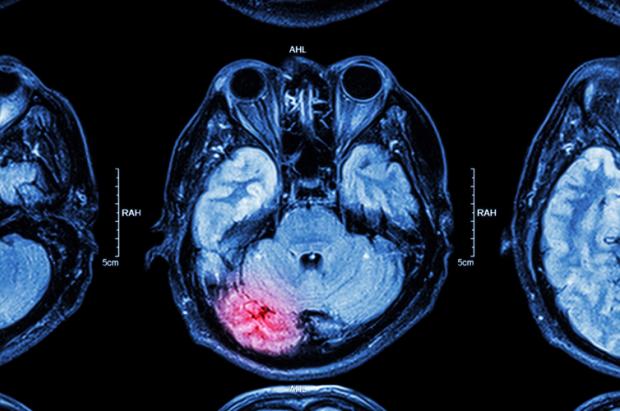

Новий аналіз генетичних даних показав: люди з варіацією групи крові А мають дещо вищу ймовірність пережити інсульт до 60 років. Йдеться про масштабне дослідження, опубліковане у 2022 році, яке охопило десятки тисяч пацієнтів із різних країн, передають Патріоти України.

Дослідники з’ясували, що саме підгрупа крові А1 демонструє статистично значущий зв’язок із раннім інсультом. Професор Стівен Кіттнер з Університету Меріленду зауважив, що кількість інсультів у молодшому віці зростає, але причини цього явища досі вивчені недостатньо.

Цікаво, що серед людей віком понад 60 років зв’язок між групою крові А та інсультом майже зникає. Це може свідчити про різні механізми розвитку хвороби в різному віці: у молодших пацієнтів інсульт частіше пов’язаний із тромбоутворенням, а не з атеросклерозом.